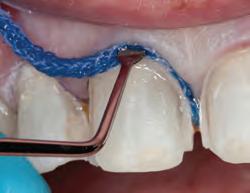

1. Packing Ultrapak cord quickly displaces tissues and improves access for indirect veneer luting.

Dr. Dan Fischer Founder, Ultradent Products, Inc.

3. After complete hemostasis has been attained, excellent retraction is achieved using Ultrapak™ knitted cord placed with the Ultrapak™ packer.

1. For restorations, Astingedent™ X hemostatic and Ultrapak cord are ideal for controlling blood and sulcular fluids and can also protect tissue from burs. Use a firm air/water spray to remove excess hemostatic solution.